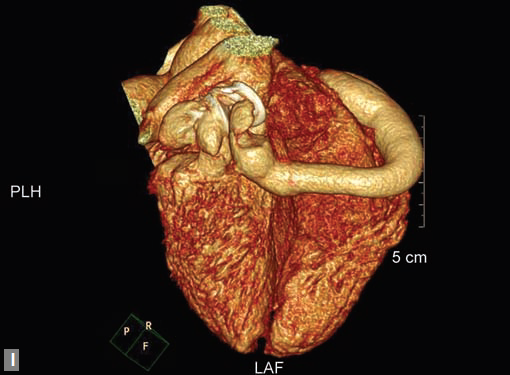

complication. Aneurysmal dilation is common in ascending

aorta (Figs 19W to Y).

CT is also useful in surveillance of diagnosed aneurysms.

Figs 19A to Y (A to C) Scannogram (A), plain (B) and contrast study (C) show partial anomalous pulmonary venous connection; (D to F) Heterotaxy; (G) Aortic occlusion; (H and I) Aortic stents; (J) Aortic dissection with ‘Benz’ sign due to second dissection within the true lumen; (K, L and M) Aortic dissection with thrombus in pseudolumen following catheter angiogram; (N) Aortic dissection involving common carotid arteries and subclavian artery; (O, P, Q and R) Aortic dissection with right renal artery arising from true lumen and left renal artery from false lumen; (S, T, U and V) Stanford B dissection with extension Y to iliac vessels; (W to Y) Aneurysmal dilation of ascending aorta